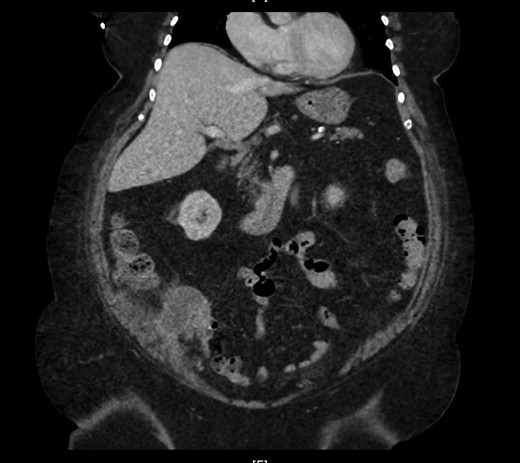

The cecum measures 8 × 6 cm and appendix is dilated and measures 7 cm × 2 cm. The mucosa at the appendicular orifice demonstrates a polypoid appearing mass measuring 3.2 × 1.5 cm (Fig. 3). Grossly the mass extends throughout the appendix and measures approximately 7.7 cm × 2 cm. The distal aspect was hemorrhagic and ragged, with an opened ragged defect measuring 1 cm in greatest dimension (Fig. 4). The majority of the appendicular serosa was tan and smooth, with scattered red areas. Grossly, the tumor is 1.5 cm from the mesenteric margin. Multiple lymph node candidates are identified. One lymph node candidate measures up to 5 mm and is 4 mm from the mesenteric margin.

A longitudinal cross section of the appendix, adenoma at appendiceal orifice on left, hemorrhagic tip rupture on right.